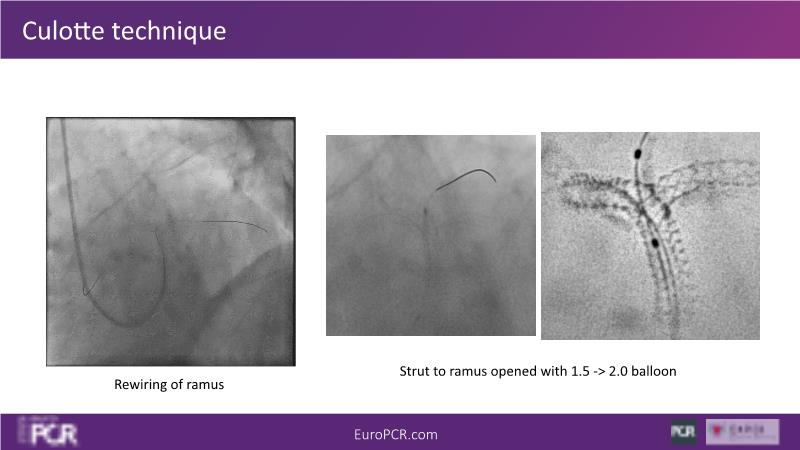

Join this session to delve into the unmet needs concerning drug-eluting stents (DES), including poor long-term clinical outcomes, with up to a 50% MACE rate at 10 years, and a non-plateauing 2-3% annual event rate. Explore how DynamX Bioadaptor technology addresses these challenges by maintaining the established flow lumen and restoring hemodynamic modulation of the artery. Discover the sustained clinical benefits demonstrated in a 2-year RCT, potentially establishing a new treatment standard for CAD patients. Gain insights into patient types benefiting most in clinical practice, such as those at higher risk of restenosis (e.g., LAD disease, long lesions, small vessels, co-morbidities), and younger patients with longer lifespans.